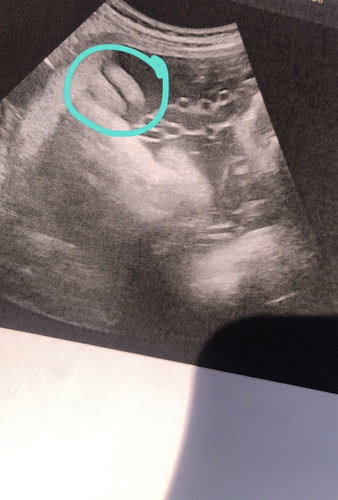

สอบถามคะในรูป เพศหญิง ใช่มั้ยคะ มีโอกาสจะเป็น เพศชายมั้ยคะพอดีผลเลือด ตรวจนิฟตี้เราเป็น เพศชายคะ มีแม่ๆคนไหนเคยเจอเหตุการณ์แบบนี้บ้างมั้ยคะ ตอนนี้น้อง 33w ค่ะ

เพราะว่าตรงที่แม่วงไว้ในรูป มันบอกเพศไม่ได้นะคะ

เราว่าที่วงไม่ใช้เพศนะน่าจะเปนขามากว่าค่ะ

จากภาพน่าจะเป็นขานะคะ เหมือนน้องนอนหันหลังให้ยุ

จากภาพไม่น่าใช่เพศนะคะ ผลเลือดน่าจะตรงกว่านะคะ